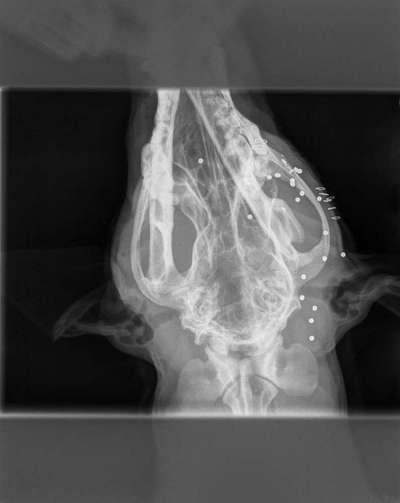

Wenn dein Hund weg ist und er am nächsten Tag vor der Tür steht. Erstmal denke ich wird jeder sowas von froh sein, wenn der Freund nach langem suchen wieder da ist. Was ist aber, wenn er schwer verletzt ist und der Tierarzt dir sagt das es eine Schußverletzung ist und es abzuwarten ist ob er es überlebt. Einer Bekannten ist es so ergangen, die Hündin ist mit ihrem Freund entwischt und stand am nächsten Tag vor der Tür. In einer OP wurde das Auge entfernt und jede Menge Blei entfernt. Es bleibt abzuwarten, ob die Hündin es überlebt, denn das Blei konnte nicht komplett entfernt werden. Eine Bleivergiftung ist tötlich. Was würdet ihr tun? Es hinnehmen oder dagegen angehen? Die Hündin hat sich nicht für Wild interessiert. Der Jäger hat genau ins Auge geschossen und ihr Rüde der hinter ihr stand hat am Ohr eine Verletzung, diese ist aber zum Glück nicht so schlimm. Ein Jäger hat leider sehr wohl das Recht zu schießen, allerdings als letzte Instanz und muß es auch auf einem Formblatt festhalten. Ich finde es widerlich und abgrundtief traurig, das ein Mensch zu so etwas fähig ist. Denn letztendlich entscheidet er als Jäger.

Leider gibt es schlechte Nachrichten..die Maus muß morgen nochmals operiert werden, da sie noch zu viel Blei im Körper hat und die Blutwerte dementsprechend sehr schlecht sind. Ich hoffe sehr auf Besserung und wünsche nur das Beste...